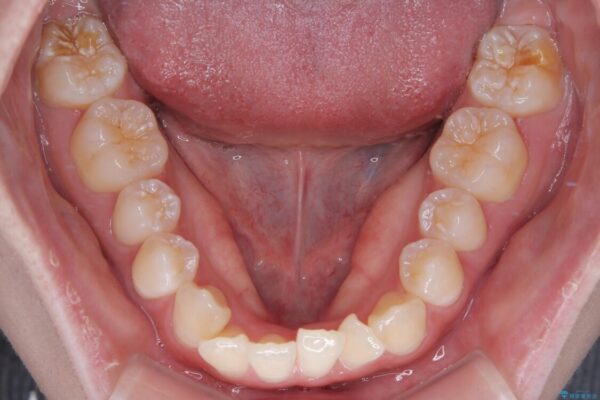

「前歯のデコボコ(叢生)をきれいに整えたい」とのことでご来院されました。

治療前

• 【モニター】前歯のデコボコをスッキリ解消!目立ちにくいワイヤー矯正でスピーディに治療完了 治療前画像